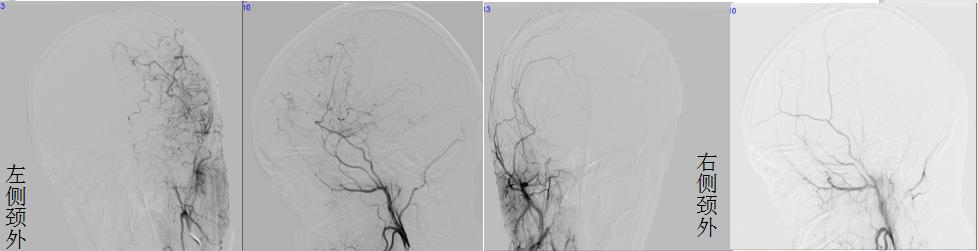

▲双侧脑血管重建术后一年复查

这次到医院复查,佳佳的精神状态非常好,让人很难把眼前这个开朗明媚的女孩与一年前那个病态十足的患者联想起来。复查影像提示:双侧脑血管重建术后,双侧颞浅动脉脑膜副动脉经软膜向颅内动脉吻合代偿。这下,佳佳一家总算是可以放心了。